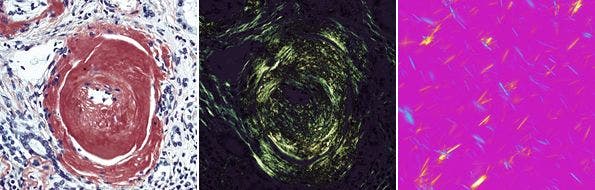

偏光観察法(P、PL:Polarized Light microscopy)

岩石、鉱物の結晶の観察や、物質の複屈折性(入射した光が2つの屈折光に分かれる性質)の検出、測定を行うのに適した観察方法である。

顕微鏡に2枚の偏光板を装着し、偏光の干渉を利用して複屈折性の存在する部分を明暗や色のコントラストに置換えて観察する。

回転ステージを用いて標本を回転させると、複屈折性のある部分が45°ごとに暗く見えたり(消光位)、明るく見えたり(対角位)する。

図16 組織切片のアミロイド観察と尿酸ナトリウムの偏光観察

図16 組織切片のアミロイド観察(左:明視野観察 中:偏光観察)と尿酸ナトリウムの偏光観察(右:尿酸結晶観察)